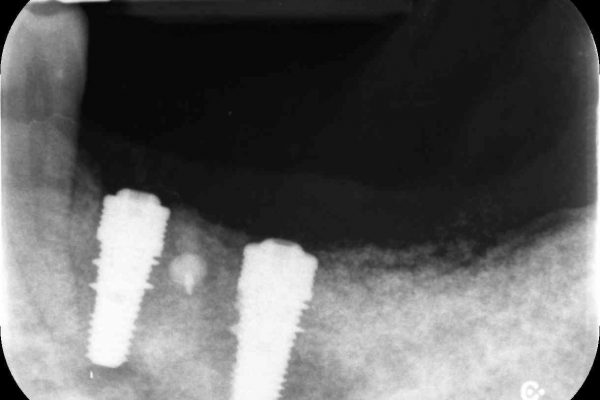

Importante perdita ossea Verticale ed orizzontale provocata dalla perdita di Impianti posizionati a causa della MANCANZA di una attenta diagnosi, piano di trattamento e capacità operativa, che avrebbero mostrato l’impossibilita di posizionare gli Impianti senza ripristinare lo spessore osseo adeguato …